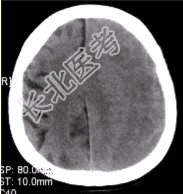

- [材料题] 男性,70岁。突发昏迷。头CT显示如下图。

A、左侧额顶部硬膜下半月形混杂密度影

B、脑皮质未见异常

C、脑皮质受压内移

D、中线结构右移

E、脑实质异常密度影

F、右侧脑沟变窄